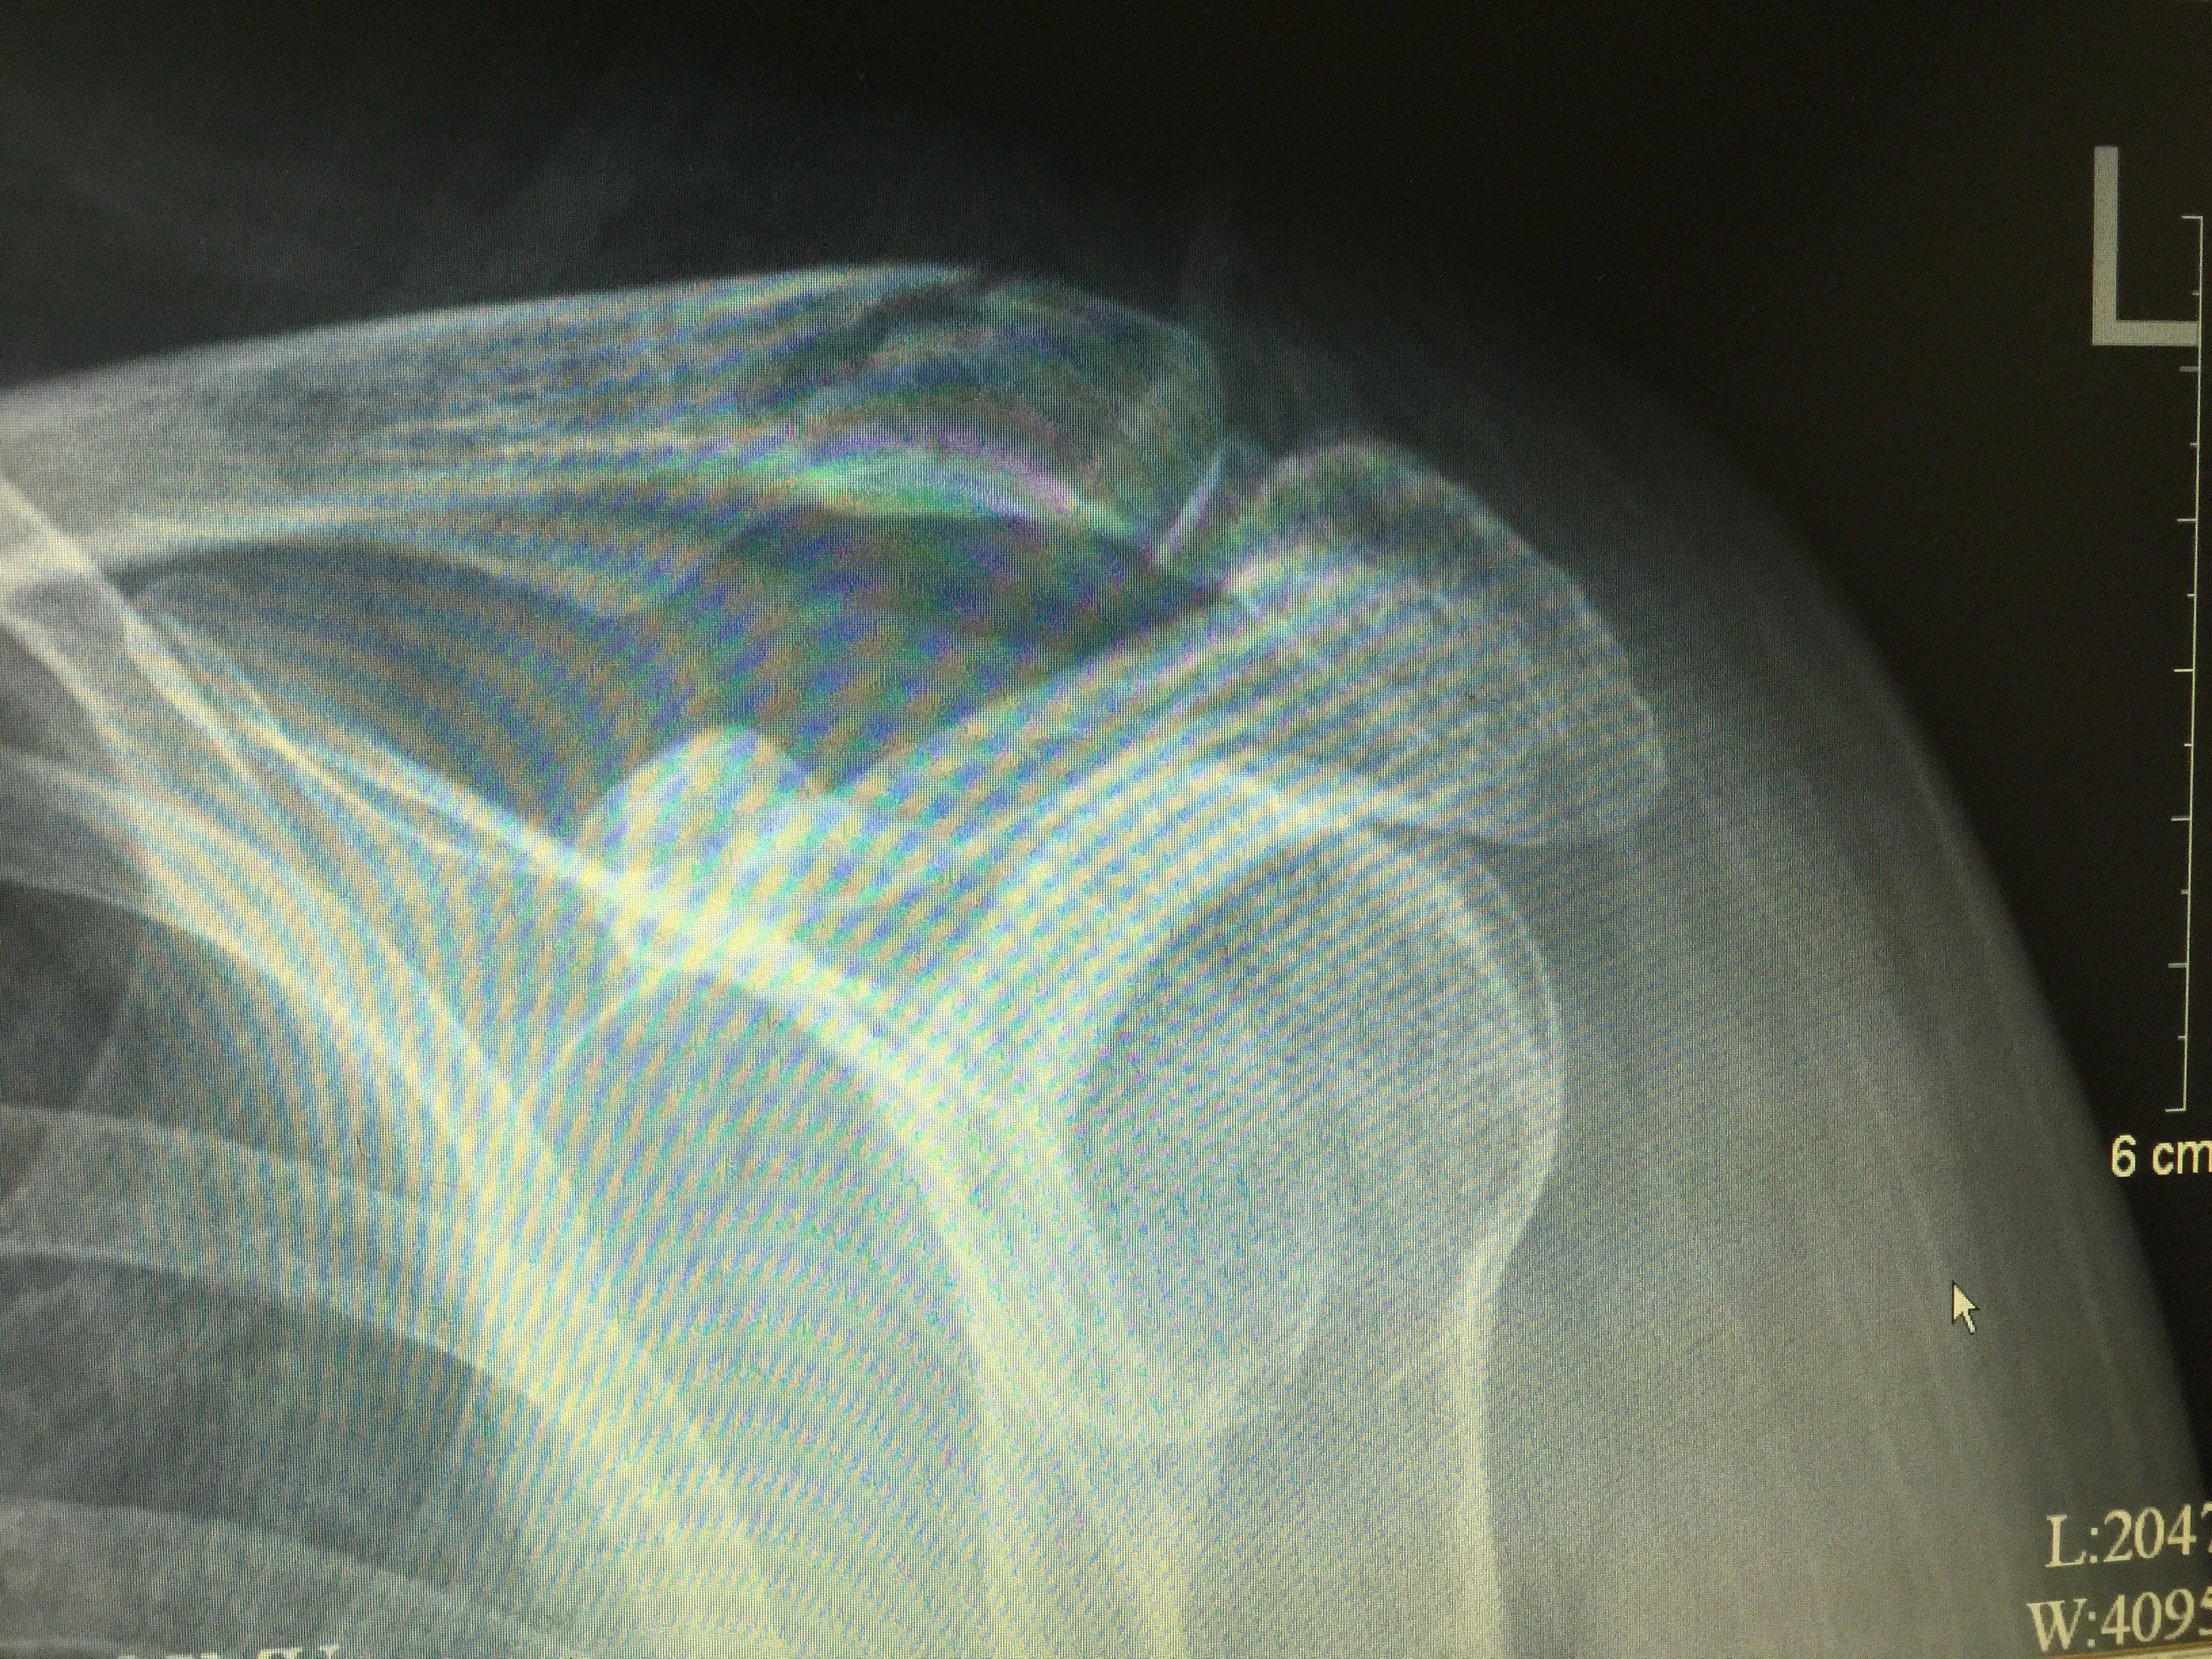

微创治疗锁骨远端骨折并喙锁韧带断裂

3264x2448 - 2747KB - JPEG